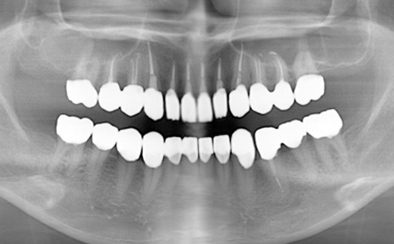

治療前

治療後

黄色い矢印の歯が治療前の対象歯です。レントゲンで観察すると、歯の根のお薬が充分には入っていないようです。

麻酔をして歯の中をマイクロスコープで観察すると、元々あった3つの根だけでなく「もう一つの4番目の根」があったのです。根管治療自体は容易に行えましたが、歯の中を明るく拡大できるマイクロスコープを持っていない歯医者さんでは見つけるのが困難だと思われます。この4つ目の歯の根を治療することにより痛みは消失し「抜歯してインプラント」になるという悪循環に陥らず済みました。根管治療はマイクロスコープを使って精密に、また丁寧に行えば歯を長く保たせることができる治療です。やはり神経自体を残すという選択が、歯の保存にとって一番良いということは間違いありません。

| 費用 | デンタルドック:55,000円 根管治療(奥歯):176,000円 MTAセメント:33,000円 歯の土台:33,000円 合計:297,000円 |